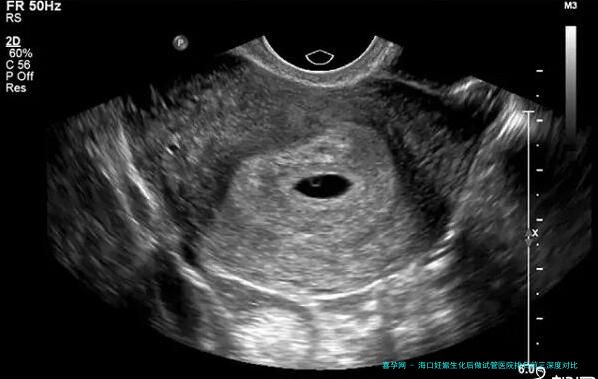

| 阴道B超监测排卵 | 1500 | 800 | 1200 | 1000-1300 |